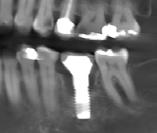

Cirujano dentista con especialidad en periodoncia e implantes dentales. Posee un fellowship oral. Miembro del Colegio de Cirujanos Dentistas de Puerto Rico y del American Association of Periodontology. Presidente de la Asociación de Periodoncistas de Puerto Rico.

La doctora Frances M. Herrero se graduó Magna Cum Laude de Bachillerato en Ciencias del Colegio de Mayagüez y Suma Cum Laude del Recinto de Ciencias Médicas, Escuela de Medicina Dental. Especialidad en Periodoncia de la Universidad de Maryland. Pertenece al Colegio de Cirujanos Dentistas; Sociedad de Especialistas en Periodoncia e Implantología de Puerto Rico, Sociedad Americana de Periodoncia y es Board eligible en Periodoncia.

Comenzó su trayectoria académica en la UPR de Mayagilez, donde obtuvo su Bachillerato en Biología. Luego continuó sus estudios en la Escuela de Medicina Dental de la Universidad de Puerto Rico de Ciencias Medicas, graduándose con su título de Doctor en Medicina Dental (DMD) en 2013. El Dr. Reinaldo Deliz Guzman está profundamente comprometido con la excelencia en la atención periodontal y se enorgullece de servir, a la comunidad local en PR,